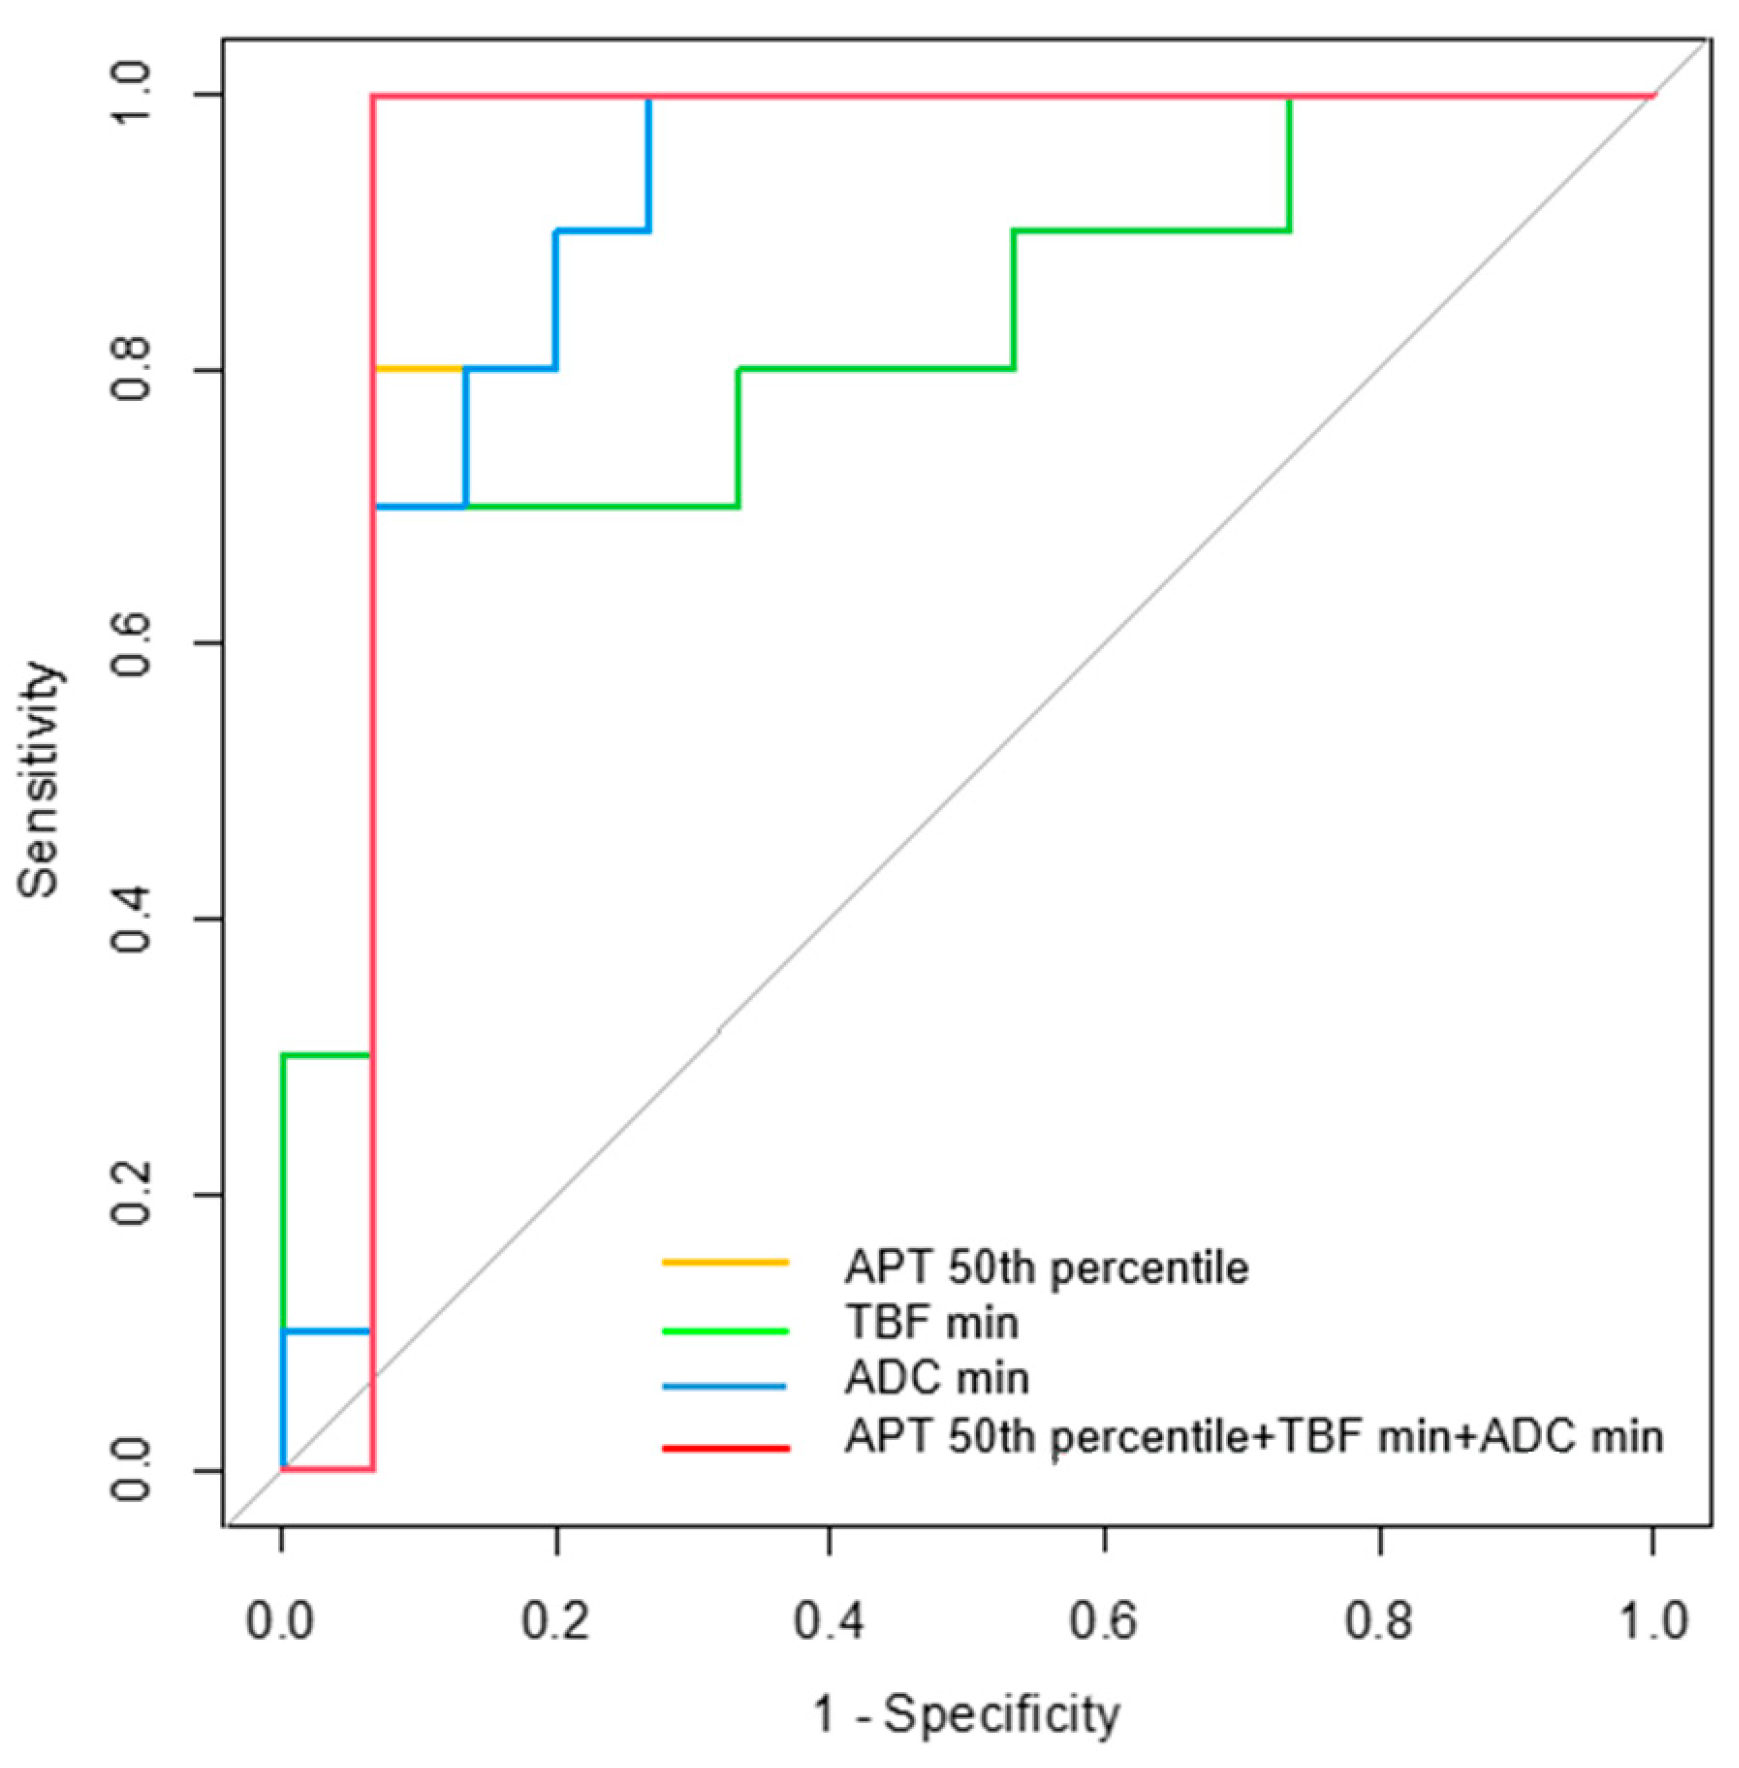

3.4. Diagnostic Performance for Differentiating MTs from BTs

4. Discussion

| Parameters | AUC | 95% CI | p-Value | Cutoff Value | Sensitivity (%) | Specificity (%) |

|---|---|---|---|---|---|---|

| APT 50th percentile | 0.900 | 0.764–1.000 | 0.001 * | 1.94 | 93.3 | 80.0 |

| TBF min | 0.813 | 0.632–0.995 | 0.009 * | 7.35 | 70.0 | 93.3 |

| ADC min | 0.900 | 0.771–1.000 | 0.001 * | 0.51 | 100.0 | 73.3 |

| APT 50th + TBF min + ADC min | 0.933 | 0.807–1.000 | <0.001 * |  |  |  |